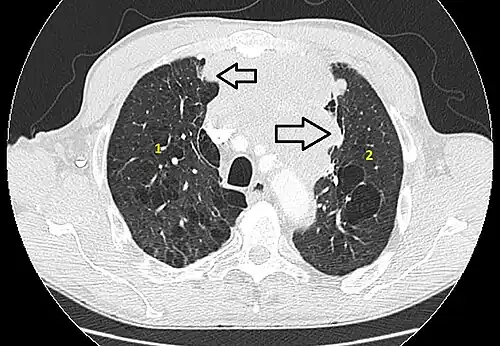

6 : sternum.- Scanner en fenêtre parenchymateuse, montrant un carcinome thymique envahissant les poumons (avec des lésions d'emphysème) au contact des deux poumons (1 : poumon droit ; 2 : poumon gauche) ;

flèches noires : zones suspectes d'envahissement.